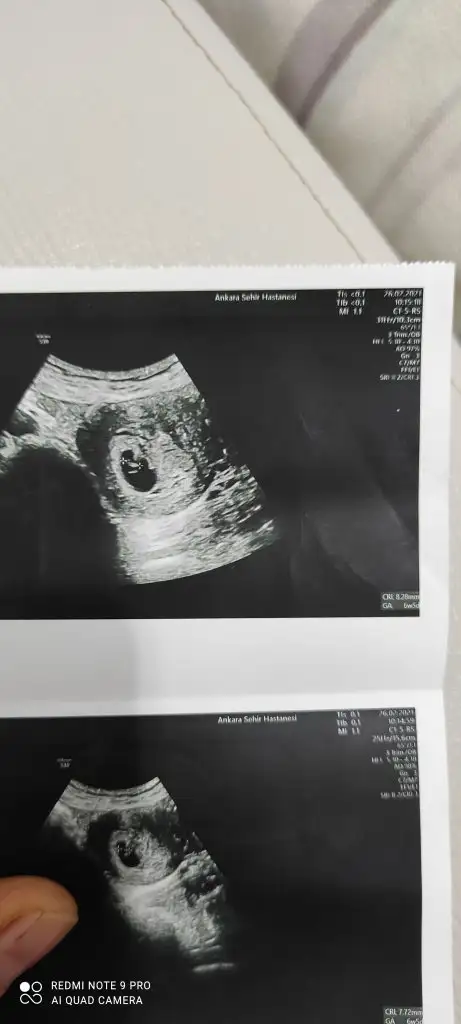

Merhabalar 7 hafta 5 günlük burada cinsiyet tahmini alabilir miyim bende karından ultrason abdominal.

IMG_20210331_101722.webp

şimdiden teşekkür ederim